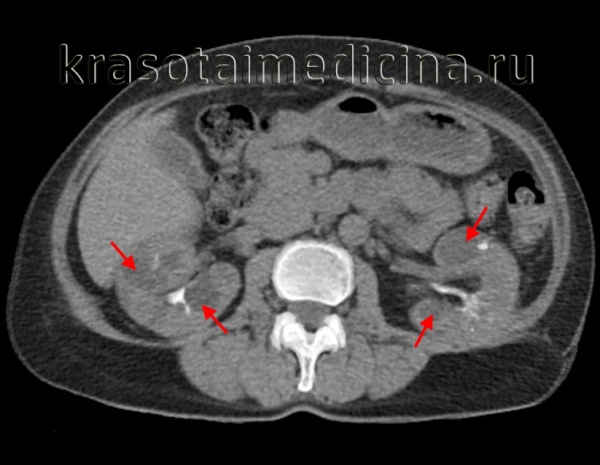

(Слева) УЗИ во фронтальной плоскости. Не совсем типичная ультразвуковая картина. Почки крупные, гиперэхогенные, содержат гипоэхогенные пирамиды. Умеренное расширение лоханки. При прогрессировании заболевания картина может измениться.

(Справа) Тот же случай. Постнатальное УЗИ во фронтальной плоскости. Более типичная картина: паренхима диффузно гиперэхогенная, утрачена нормальная структура мозгового вещества. Данный случай иллюстрирует разнообразие ультразвуковых находок при АРПКП.

(Слева) Другой случай АРПКП. УЗИ в сагиттальной плоскости. Визуализируются увеличенные гиперэхогенные почки (калиперы). Нормальная гипоэхоген-ная кора сохранена. Это довольно характерная находка, но обнаружить ее на пренатальном УЗИ бывает трудно.

(Справа) Посмертная МРТ, Т2-ВИ, фронтальная плоскость. Грудная клетка очень малых размеров. Почки значительно увеличены, нормальная паренхима отсутствует. Расширенные канальцы имеют гиперинтенсивный сигнал.